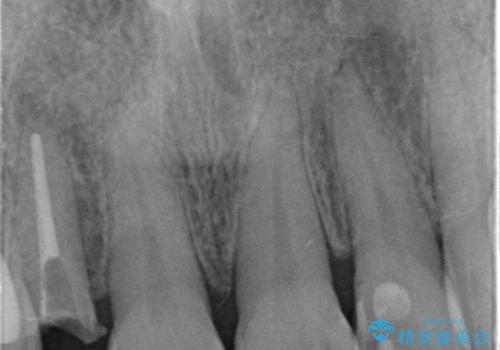

- 右上の前歯が取れたとのことで来院された患者様です。

再根管治療からのやり直しをご提案しましたが、ご希望されなかったため土台(コア)のやりかえからとなりました。